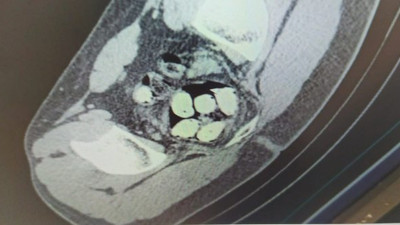

Erzincan'da yurt dışından uyuşturucu madde getirdikleri belirlenen İran uyruklu üç kişi jandarma ekiplerince yakalandı. Yapılan muayenede midelerinde uyuşturucu kapsülleri sakladıkları belirlenen şüpheliler gözaltına alındı.